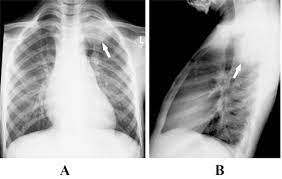

Tuberculosis Mimicking Lung Cancer Sciencedirect from ars.els-cdn.com 90% of cases being attributable to smoking. Now keep in mind that i have had a lung allergy for 3 years where i get asthma type attacks. Iteither enlargesas disease progresses or, much. Lung cancer and tuberculosis (tb). Lung cancer is the leading cause of cancer death worldwide, with approx. Why has this disease, once thought to be confined to the. It has recently become more common, and treatment is far from easy. Tuberculosis, a disease that used to be common in the uk and other western countries, was thought to have been successfully controlled when vaccination was introduced.

Interestingly so, tuberculosis has been known to mimic lung cancer due to its presentation in the form of pulmonary infiltrates and mediastinal lymphadenopathy however, in the reported cases where pulmonary tuberculosis was mistaken for pulmonary malignancy, a number of different, costly.